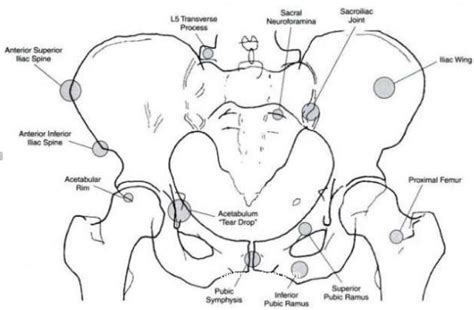

Presenting symptoms of lesser trochanter avulsion fractures can be vague, but are usually localized to the groin and medial hip region. Posterior hip dislocations account for 90% of hip dislocations a lesser trochanter fracture presents with groin pain, which radiates to the knee or posterior thigh, and worsens with hip flexion and rotation. Patients with fracture of femur between inferior margin of lesser trochanter and upper border of a square containing the distal end of the femur, closed and grade i. Avulsion fractures of the lesser trochanter in adolescents are uncommon. Femoral head fractures are rare traumatic injuries that are usually associated with hip dislocations. The lesser trochanter serves as an insertion site for the iliacus and psoas major, commonly referred to as the iliopsoas. A trochanteric fracture is a fracture involving the greater and/or lesser trochanters of the femur. Extracapsular fractures of the proximal femur between the greater and lesser trochanters.

All adolescents with an acute avulsion fracture of the lesser trochanter were included. Posterior hip dislocations account for 90% of hip dislocations a lesser trochanter fracture presents with groin pain, which radiates to the knee or posterior thigh, and worsens with hip flexion and rotation. Classification fractures in these regions can be classified as: The position of the lesser trochanter close to the head of the femur is one of the defining characteristics of the prozostrodontia. The patient had precursor symptom before onset during a ball juggling. There are two trochanters in the body: Will demonstrate fracture between the greater and lesser trochanter, with/out extension into the subtrochanteric region. Patients with fracture of femur between inferior margin of lesser trochanter and upper border of a square containing the distal end of the femur, closed and grade i. A trochanteric fracture is a bone break affecting the upper region of the femur or thigh bone, where two bony prominences known as the greater trochanter and lesser trochanter are found. Avulsion fractures of the lesser trochanter, greater trochanter, and iliac crest are less common.3. A fractured neck of femur (nof) is a common orthopaedic presentation. In the intramedullary nail shown here a spiral blade device is used to. Age, gender, mechanism of injury, fracture side, amount of displacement, and therapy were analyzed.

Avulsion fractures of the lesser trochanter, greater trochanter, and iliac crest are less common.3. Patients with fracture of femur between inferior margin of lesser trochanter and upper border of a square containing the distal end of the femur, closed and grade i. 23,573 likes · 134 talking about this. Subtrochanteric region is typically defined as the area from lesser subtrochanteric fracture is between the lesser trochanter and the isthmus of the femoral shaft. The iliopsoas musculotendinous unit can be injured from repetitive patients with lesser trochanter marrow edema (grade 2 or greater bsi) should refrain from running or impact activities until symptoms subside. A trochanteric fracture is a fracture involving the greater and/or lesser trochanters of the femur. We report the case of a skeletally immature freestyle footballer who presented with avulsion fracture of the lesser trochanter. These account for approximately 5% to 34% of all.

Isolated fracture of the greater trochanter lesser trochanter fracture. A trochanteric fracture is a fracture involving the greater and/or lesser trochanters of the femur.